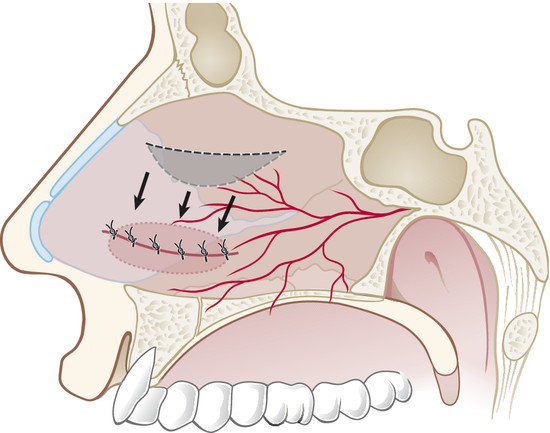

In the case of rounded perforations, a rotation/advancement mucoperiosteal flap is designed by a rounded incision based posteriorly on the nasal-septal artery and elevated up to 1 cm from the choana (Fig. 19‑4). Also, in this case the flap is rotated to reach the inferior border of the perforation and sutured with a 3–0 Vicryl suture (Fig. 19‑5).

The mucoperiosteal graft is then inserted through the hemitransfix incision in the tunnel between the septal cartilage and elevated septal mucoperichondrial flap (Fig. 19‑8).

Graft borders are positioned under the previously elevated perforation borders in underlay fashion for minimum 5 mm all around (Fig. 19‑9).

At the end of this step, no one area of the perforation has to be uncovered (Fig. 19‑10).